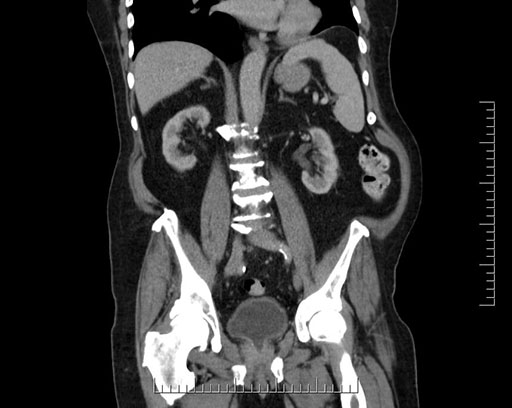

Whipple (pancreaticoduodenectomy) [case 7]

Imaging Analysis

Look through the patient's CT scan to identify any areas of concern for the necessary procedure.

Based on your CT findings, which issue(s) would give reason for "planned slowing down moment(s)" in this case?

Considering a standard Whipple procedure, what step(s) of the operation would you do differently in this case?